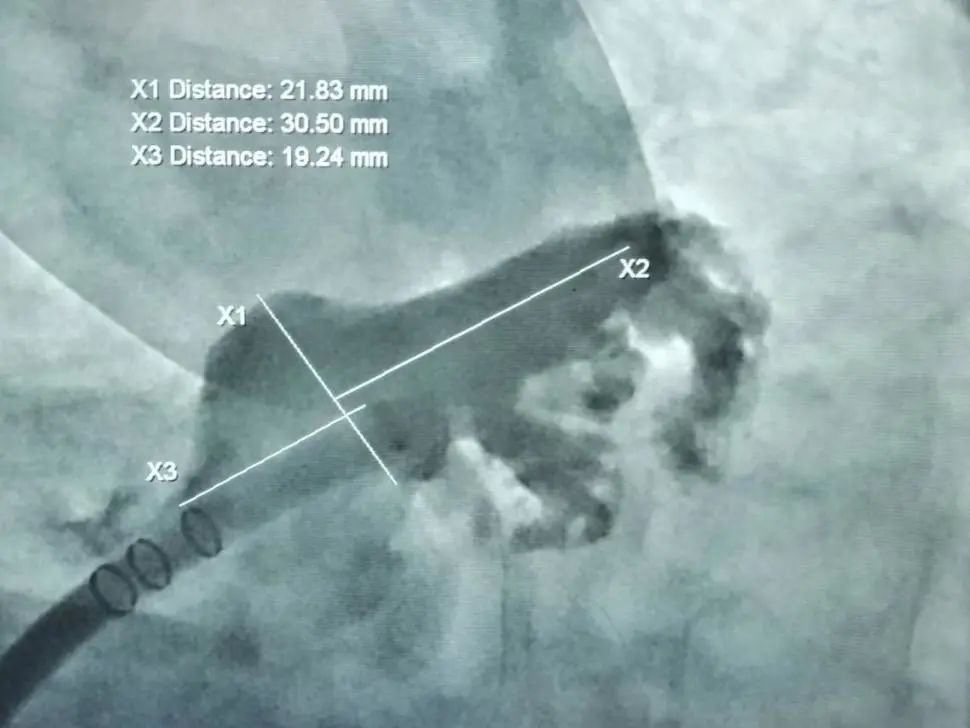

病例3:持续性房颤冠脉造影+左心耳封堵治疗

男,73岁。全麻加TEE下进行冠脉造影+左心耳封堵术。冠脉造影提示正常,TEE测量左心耳开口17-21mm。造影观察左心耳呈不规则仙人掌型,DSA测量左心耳开口19mm,深度20mm。选用WATCHMAN 24mm封堵器封堵。展开封堵器后,造影和TEE下观察封堵效果理想,无残余分流,牵拉试验稳定,测量压缩比16%,满足PASS原则,封堵器释放。